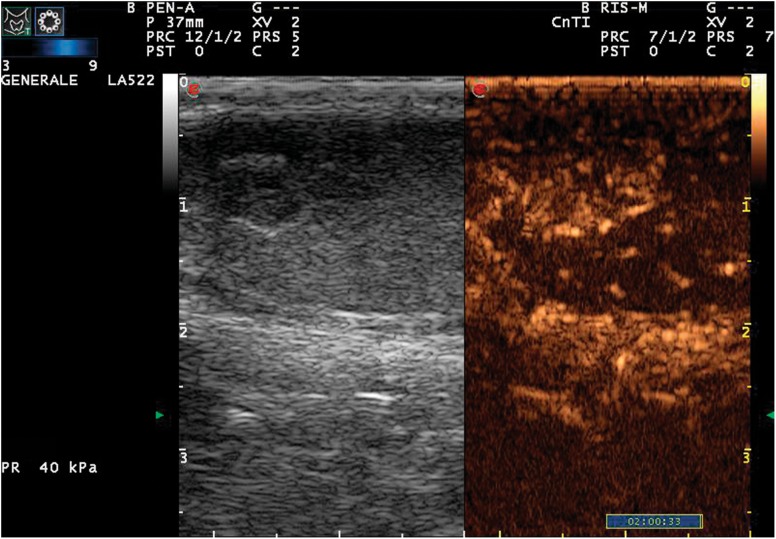

CEUS showed vascularization in 5/19 lesions thereby increasing the specificity of the method. Three lesions were negative at CEUS, but they were linked to inflammatory disease. The results obtained in this study show that CEUS enhancement indicates the presence of an active lesion, which requires histological examination to be accurately characterized (Fig. 2).

Fig. 2.

Qualitative CEUS imaging. Longitudinal scan 30 s after first injection, presence of strong enhancement within the lesion